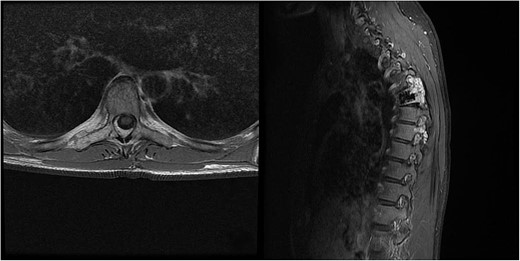

Three and a half years prior to admission to our institution, the patient underwent emergent Th6 vertebroplasty with laminectomy for a radiologically characteristic and histologically confirmed Th6 AVH causing acute thoracic myelopathy with a week-long paresis of the right foot dorsiflexion, performed by another surgeon. A progressive kyphotic deformity of the Th6 vertebrae was observed on radiographic follow-ups, whereby the hypoesthesia on the right anterior thigh persisted (ASIA score D, VAS pain score 7). Follow-up MRI and CT imaging revealed recurrent AVH of the Th6 vertebrae expanding into the spinal canal, leading to newly recognized worsening of myelopathy (Fig. 1). Additionally, a concomitant haemangioma was observed in the right transverse and articular process of Th8 (Fig. 2).

Follow-up CT imaging revealed recurrent AVH of the Th6 vertebrae, MRI scan showing AVH expanding into the spinal canal and causing myelopathy.